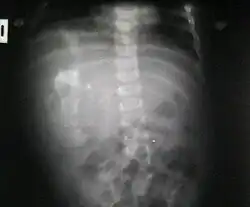

Fetus in fetu

Fetus in fetu (or foetus in foetu) is a rare developmental abnormality in which a mass of tissue resembling a fetus forms inside the body of its twin. An early example of the phenomenon was described in 1808 by George William Young.[1]

Fetus in fetu may be a parasitic twin fetus growing within its host twin. Very early in a monozygotic twin pregnancy, in which both fetuses share a common placenta, one fetus wraps around and envelops the other. The enveloped twin becomes a parasite, in that its survival depends on the survival of the host twin, by drawing on the host twin's blood supply. The parasitic twin is anencephalic (without a brain) and lacks some internal organs, and as such is unable to survive on its own.